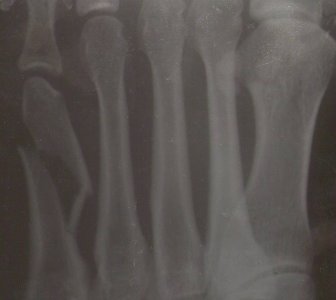

Здравствуйте. 1 июня неудачно подвернула ногу и в результате - перелом основания пятой плюсневой кости без смещения (краевой перелом?).

Наложили гипсовую лонгету, потом для удобства заменила на пластиковый гипс. Врач сказал, что можно аккуратно ходить. Сегодня ( прошло 6 дней) нога не болит, отек почти прошел, гематома на пальцах.

Наступать можно, контрольный снимок через 10 дней и 6 недель. Возможны варианты.